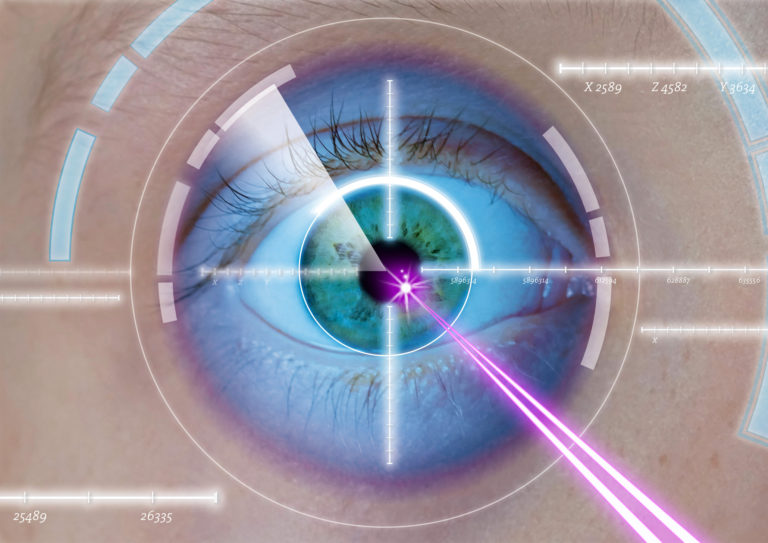

Les techniques de chirurgie réfractive